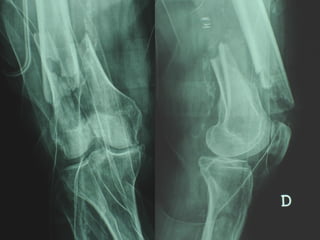

INDICAZIONI COMUNI Fratture sovracondiloidee Fratture intercondiliodee Fratture diafisarie distali PARTICOLARI Fratture con grave osteoporosi Fratture periprotesiche

VANTAGGI CHIRURGIA MININVASIVA Mini Open Inserimento della placca sottocutaneo per scivolamento Viti percutanee Preservazione dei tessuti molli Ridotto danno vascolare Rapida ripresa funzionale

F, 68 y

LISS  NCB

NCB

Conclusioni Riduzione  anatomica Minimo trauma chirurgico Corretto equilibrio fra elasticità e stabilità Precoce mobilizzazione